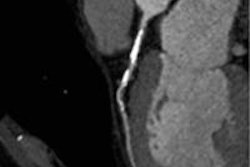

Following administration of 370 mgI/mL iopamidol (Iopamiron 370, Bayer Healthcare Pharmaceuticals) at 5 mL/sec, patients were scanned using dual-source CT (Somatom Definition Flash, Siemens Healthcare). The 30 patients were randomized (15 each) to either 80 kV and 370 mAs or 100 kV and 300 mAs. Dynamic stress images were acquired in 1-mm increments over 30 seconds to visualize the myocardium, followed by prospectively gated coronary CT angiography (CCTA) in 0.75-mm increments to visualize the coronary arteries, the study team wrote.

The investigators started the dynamic myocardial CTP scan six seconds before arrival of the contrast medium bolus in the ascending aorta. They initiated myocardial CTP three minutes after administration of adenosine at 0.14/mg/kg/min. Dynamic data were acquired using ECG-triggered axial acquisitions repeated at two table positions for z-axis coverage of 73 mm, the group wrote.

Fujita and colleagues reconstructed images every 1 mm using a B23 kernel, which includes beam-hardening correction, and examined them on a perfusion imaging workstation (Syngo VPCT body, Siemens). MBF was estimated using a parametric deconvolution technique, and the algorithm generated an MBF map.